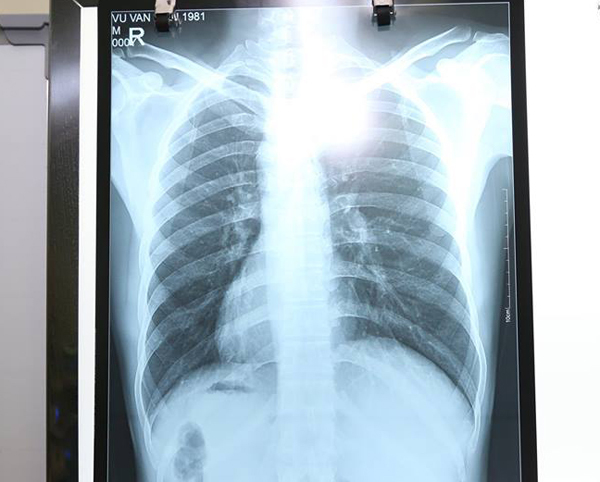

BS Nguyễn Sơn Hà, Trưởng khoa Ngoại Tổng hợp, BV đa khoa Đức Giang cho biết, nam bệnh nhân Vũ Văn H, 37 tuổi, sống tại Cổ Bi, Gia Lâm, Hà Nội vào BV cấp cứu do đau bụng vùng thượng vị và hố chậu trái, đau âm ỉ tăng dần.

Bệnh nhân được chỉ định siêu âm ổ bụng, chụp X-quang, xét nghiệm máu… Kết quả khẳng định bệnh nhân bị viêm ruột thừa cấp với đầy đủ triệu chứng như hội chứng nhiễm trùng, phản ứng thành bụng...

Tuy nhiên, điều khiến các bác sĩ kinh ngạc là tim cùng các phủ tạng khác trong lồng ngực và bụng của bệnh nhân đều ở vị trí ngược so với bình thường, tim và dạ dày đều ở bên phải còn gan, ruột thừa nằm ở bên trái.